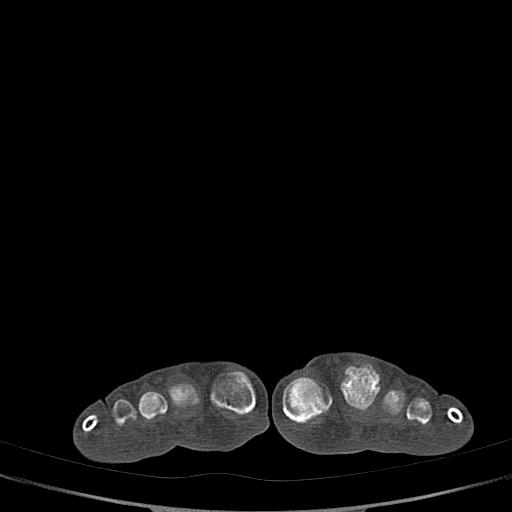

标题: CT13415:M72Y,跖趾关节病变,请会诊 [打印本页]

标题: CT13415:M72Y,跖趾关节病变,请会诊

男72岁左侧跖趾关节肿痛15年,查压痛。

骨软骨瘤可能性大,请上传x光片.

考虑退行性骨关节病。